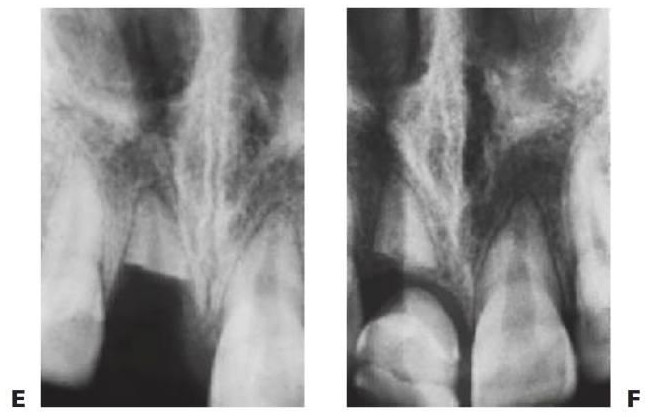

Las lesiones intrusivas (v. fig. 7.11E, F) son las lesiones más comunes en los incisivos temporales superiores. Los incisivos recién erupcionados suelen recibir la fuerza completa de cualquier caída de un niño que está aprendiendo a andar. Suele haber un desplazamiento palatino y superior de la corona, lo que significa que el ápice del diente se expulsa fuera del folículo permanente.

Tratamiento

- Si la corona es visible y sólo hay daño alveolar menor, dejar que el diente reerupcione.

- Si todo el diente se ha intruido, extraerlo.